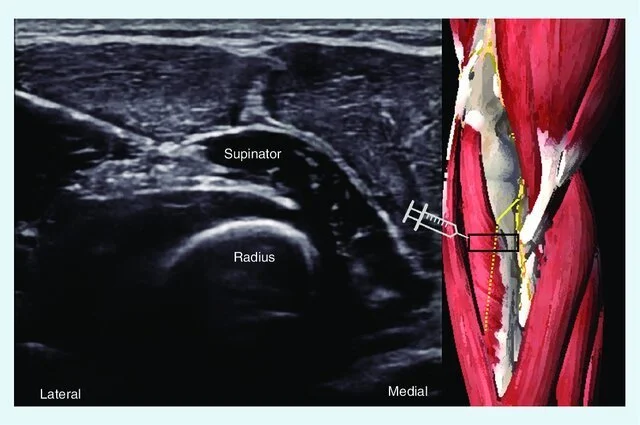

Image Credit: Ultrasound imaging and guicdance in peripheral nerve entrapment: hydrodissection highlighted, March 2020, Pain Management 10(3)

Ultrasound-Guided Nerve Hydrodissection

Nerve hydrodissection is a minimally invasive procedure is designed to address nerve-related pain and dysfunction due to nerve entrapment.

Hydrodissection involves the careful injection of fluid, often a saline solution or dextrose, around a targeted nerve to under the guidance of ultrasound imaging.

This advanced procedure allows precise visualization of the nerve and adjacent structures in real-time, ensuring accuracy and safety during the intervention.

By addressing nerve-related pain and dysfunction at its source, this procedure promotes a more focused and effective treatment